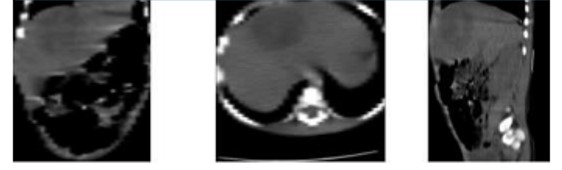

The fundamental idea with the unenhanced CT scan was to check whether the space-occupying lesion correlated with a liver abscess; for this, the lesion was to submit with the shape of a peripheral pseudo-capsule showing rim enhancement. As can be seen in Figure 2, the theoretical shape associated with abscesses on computerized tomography scans was unable to verify in this first non-contrast imaging study.

Further, in Figure 2, the appearance of the hepatic space-occupying lesion was of a heterogeneous solid lesion, which implies that CT scan without contrast, in this case, it does not allow to differentiate a complex necrotic and cystic cancer from a liver abscess. So far, no other explanation for the symptoms in the current case was discovered despite thorough gastroenterologic, infectology, surgery, and paraclinical examinations. Table 2 shows paraclinical of the laboratory.